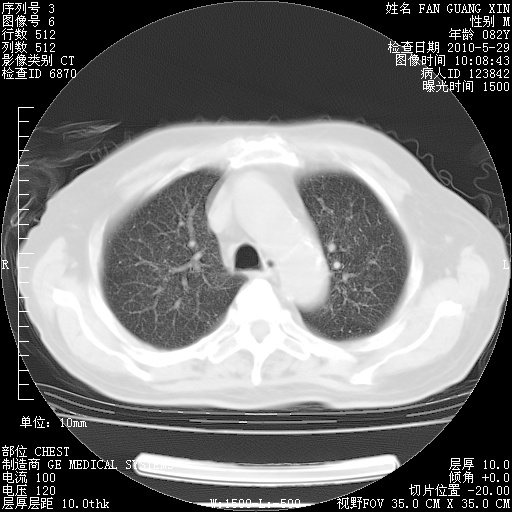

还需要哪些辅助检查?我们医院排除真菌感染没有任何检验方法,胸片好像能够排除肺部真菌感染。

补充:ENA化验全部阴性。免疫五项(IgG、IgA、IgM、C3、C4)只有C4略高。